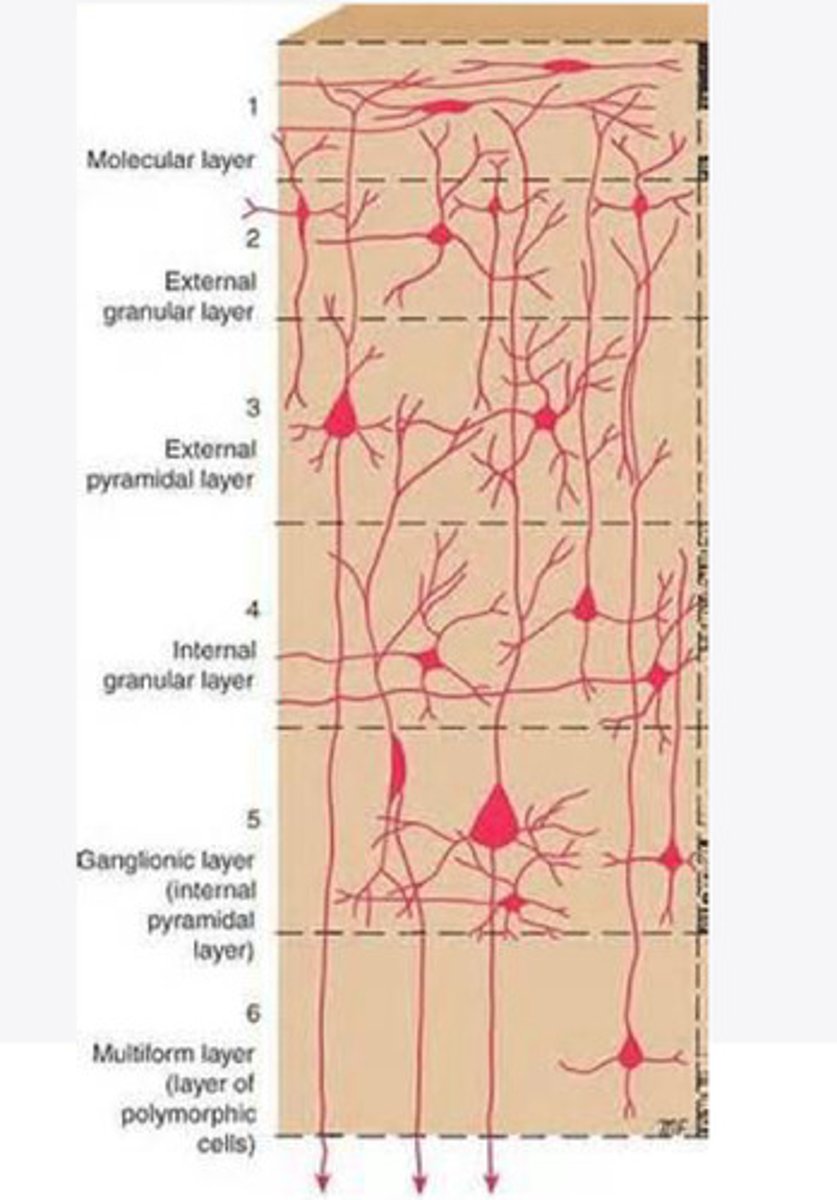

divided into 6 distinct layers, due to varying densities of cell body types within each layer

The cortex of the brain is divided into how many layers? Why is it divided into layers?

Layers of the cortex of the brain pic

2 and 4

What are the layers of the cortex that are associated with input?

3 and 5

What are the layers of the cortex that are associated with output?

molecular layer

What is the name of Layer 1 of the cortex of the brain?

very few cells

Does Layer 1 of the cortex have a lot or few cells?

receives dendrites from internal layers so it may actually function as a coordinating center where layers can communicate action

What does Layer 1 of the cortex do?

1

Every layer sends densities to Layer ____?

1

What layer serves as the "water cooler" of the brain?

external granular layer

What is the name for layer 2 of the cortex of the brain?

receives input from other cortical regions

What is the function of Layer 2 of the Cortex of the brain?

Stellate

What type of cells (stellate/pyramidal) would be most concentrated in Layer 2?

external pyramidal layer

What is the name for layer 3 of the cortex of the brain?

sends output to the other cortical layers

What is the function of Layer 3 of the cortex of the brain?

pyramidal

What type of cells (stellate/pyramidal) would be most concentrated in Layer 3 of the brain?

Layers 2 and 3

What layers are associated with association and commissural fibers?

Layer 3 - axons of cell bodies

Layer 2 - synapse into target areas in Layer 2

What part of the axons is in Layer 2/ in layer 3?

Layer 3 - external pyramidal layer

All axonal cel bodies for association and commissural fibers lie within what layer of the Cortex of the brain?

internal granular

** or called the striate cortex because it is so thick that you can see a line through this layer even in unstrained brain slides

What is the name for the 4th layer of the cortex of the brain?

receives input from the thalamus, geniculocortical layer, and other brainstem areas

What is the function for the 4th layer of the Cortex of the brain?

very thick within the vision, auditory, and somatosensory areas

Is Layer 4 thick or thin within SENSORY areas of the cortex?

Internal pyramidal

What is the name for Layer 5 of the cortex of the brain?

sends axons to the brainstem (corticobulbar) and spinal cord (corticospinal)

What is the function of Layer 5 of the cortex of the brain?

in motor areas of the cortex?

Where is layer 5 very thick in the brain?

the frontal lobe -- very motor heavy

What lobe of the brain will have a thick layer 5 of the cortex of the brain?

the multiform layer

What is the name of layer 6 of the cortex of the brain?

-sends axons back to the thalamus through corticogeniculate fibers

-modulates what information the thalamus sends to the cortex to control the strength of the signal received and modulate what you pay attention to

What is the function of layer 6 of the cortex of the brain?

no

Is layer 6 a motor layer?